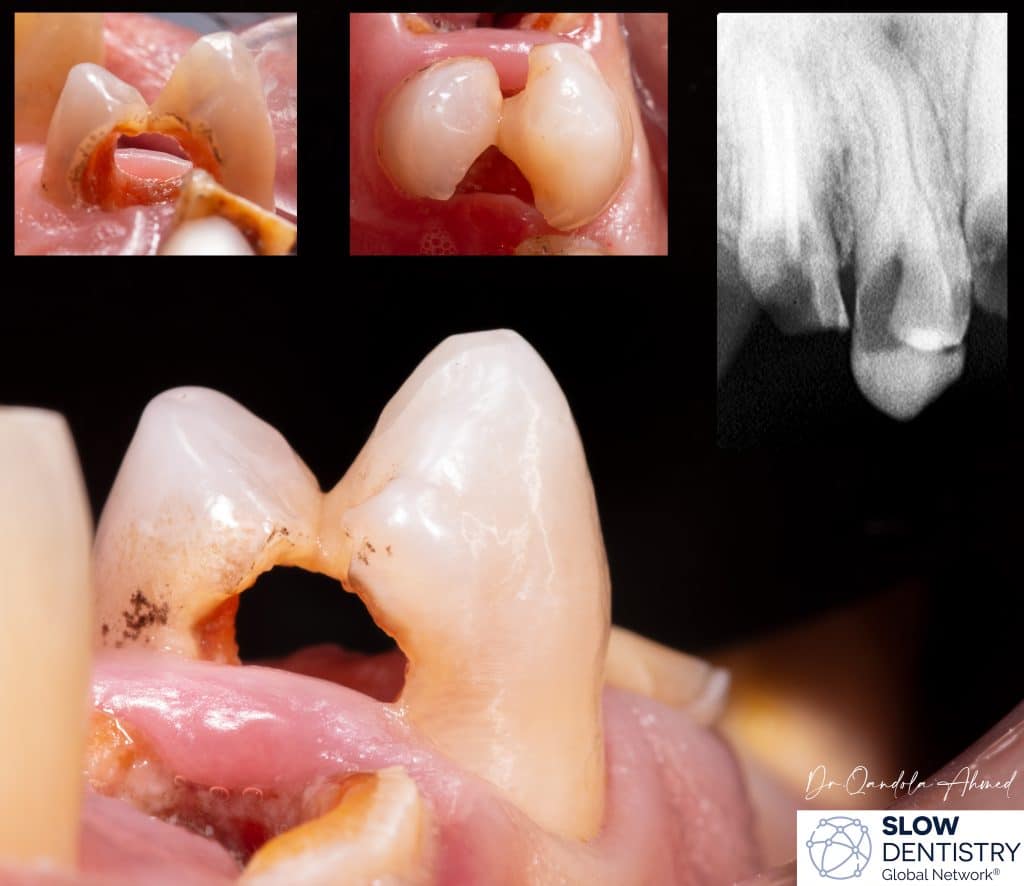

extensive caries criss-cross upper first premolar ,patient came in with severe pain , Radiograph shows a periapical radiolucency .

here's how conservative dentistry doesn't mean to remove less of tooth structure , to preserve structural integrity might require removing compromised portions of the tooth, This step is essential to prevent future fractures or breakage of the tooth.

intracanal medication was placed for 1 week .